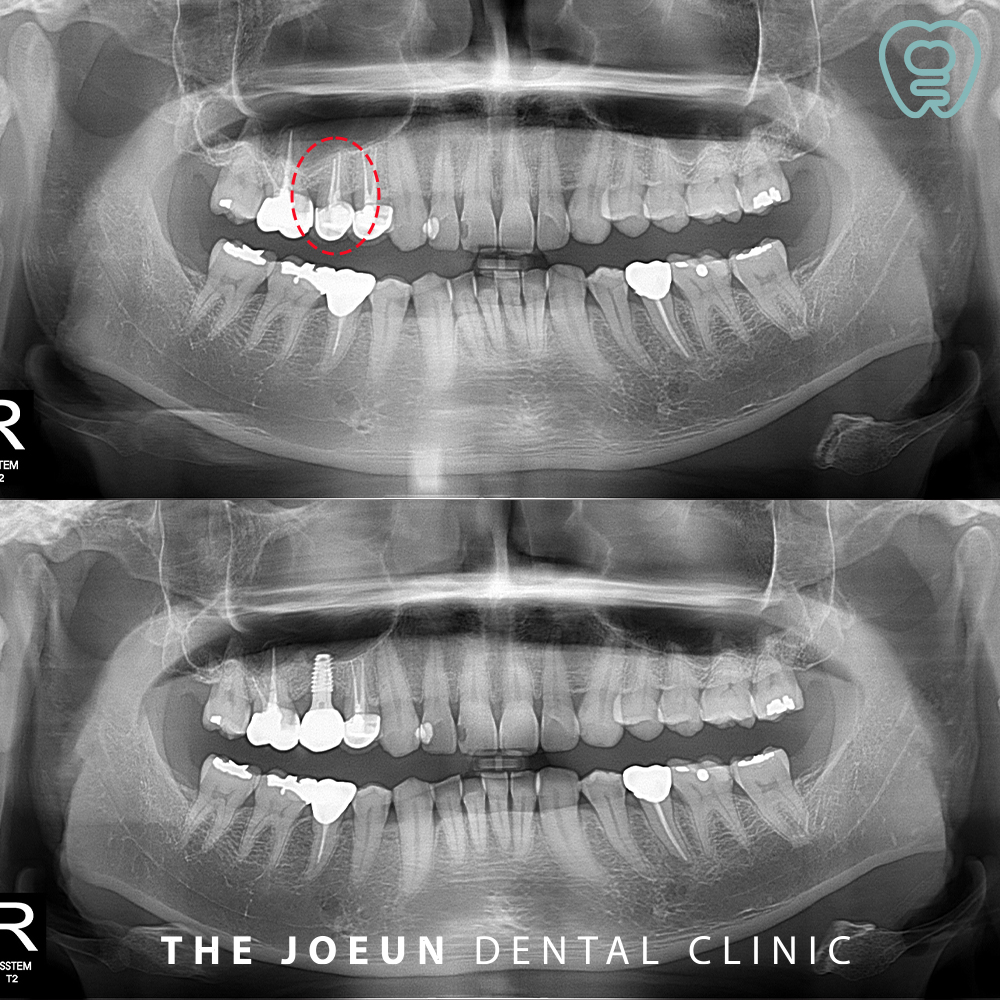

오늘은 염증으로 인해 잇몸뼈가 많이 녹아 있는 치아를 발치한 후 상악동 거상술 및 즉시 식립을 6개월의 기간 안에 완성하신 환자분을 소개해 드리도록 하겠습니다.

환자분께서는 오른쪽 위 어금니 부위로 양치를 할 때 피가 자주 나고, 양치를 하고 나서도 찝찝한 느낌이 드신다며 내원해 주셨는데요. 신경치료 후 크라운으로 씌워져 있는 작은 어금니 부위였고 겉으로 보기에는 큰 문제가 없어 보였지만 잇몸의 깊이를 측정해 보았을 때 염증으로 인해 뼈가 많이 녹아 있음을 확인할 수 있었습니다. 따라서 기존의 자연치를 발치하고 내려와 있는 상악동막을 들어 올려 뼈이식 후 임플란트 식립을 진행하기로 계획하였습니다.

치료를 시작한 지 약 6개월 만에 최종 보철물까지 완성한 모습입니다.